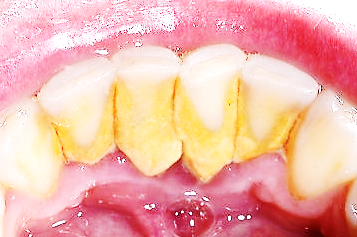

치석이 만들어지는 원인은 식사 후에 치아와 잇몸 경계 부위 그리고 치아 사이에 양치로 제거되지 않은 음식물 찌꺼기와 프라그가 남게 되는데요.

오랜 시간이 지나면서 침 속의 칼슘, 인과 반응해서 돌처럼 굳어 치석이 됩니다.

치석 위에 다른 음식물 찌꺼기가 계속 달라붙어 점점 커지게 됩니다.

한번 생성된 치석은 칫솔질이나 워터픽으로 절대 제거되지 않습니다.

치석은 치과에서 스케일링으로만 제거할 수 있습니다.